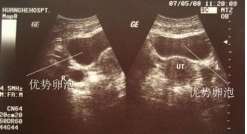

查看全文哈尔滨地贫做第三代试管婴儿不携带(哈尔滨哪里可以做试管) 确定有无排卵:检测有无排卵的方法很多,但最实用的还是 […]